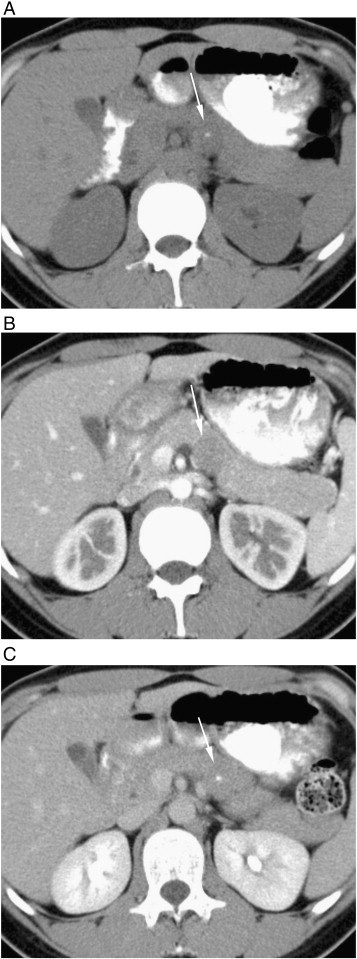

Fig. 8. A 13-year-old woman with SPN of the pancreas presented with blunt abdominal trauma and abdominal pain. (A and B) Excretory-phase axial images show hemoperitoneum around spleen and liver (arrowheads) and heterogeneous soft tissue density mass (arrows) in the left upper abdomen. Note irregular contour of the mass (arrows) suggesting rupture of capsule. The patient was treated conservatively. (C) Venous-phase axial CT performed 21 months later shows well-encapsulated large cystic mass with peripheral areas of contrast enhancement (arrows). Pathologically, it was 10 cm SPN of the pancreas with extensive hemorrhage and necrosis.